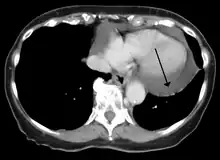

Cardiac CT and MRI scans: cross-sectional imaging with computed tomography (CT) can help localize and quantify the effusion, especially in a loculated effusion (an effusion contained to one area).[12] CT imaging also helps assess for pericardial pathology (pericardial thickening, constrictive pericarditis, malignancy-associated pericarditis).[1] Whereas cardiac MRI is reserved for patients with poor echocardiogram findings and for assessing pericardial inflammation, especially for patients with continued inflammation despite treatment.[5] CT and MRI imaging can also be used for continued follow up on patients.

A CT scan showing a pericardial effusion

A large anechoic (black) pericardial effusion as seen on ultrasound. Closed arrow: the heart, open arrow: the effusion- Pericardial effusion due to malignancy. Note bulbous heart and primary lung cancer in right upper lobe.